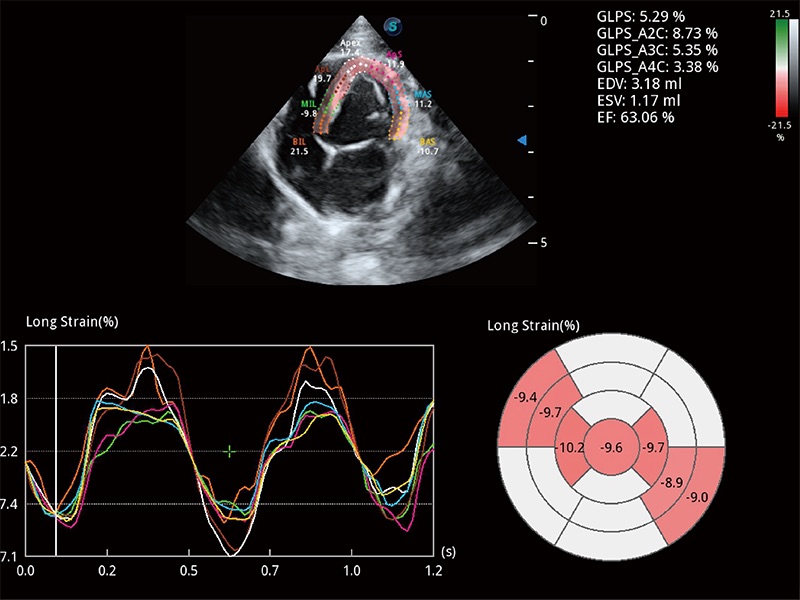

通過(guò)心肌識(shí)別技術(shù)與二維斑點(diǎn)追蹤技術(shù)相結(jié)合,對(duì)心臟的超聲圖像進(jìn)行量化分析。計(jì)算心肌17個(gè)節(jié)段的應(yīng)變、應(yīng)變率、速度、位移等,并通過(guò)牛眼圖的形式進(jìn)行呈現(xiàn)。

能夠基于左心室壁追蹤和辛普森法,自動(dòng)計(jì)算射血分?jǐn)?shù),支持多個(gè)可移動(dòng)點(diǎn)描跡,與手動(dòng)測(cè)量相比,極大節(jié)省了動(dòng)物醫(yī)生的時(shí)間和精力。